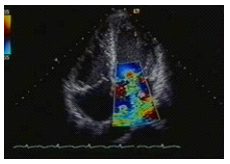

Transthoracic Echocardiogram

The standard echo (tranthoracic echocardiogram) uses ultrasound to look at the structure and function of the heart. It takes about twenty minutes and is performed on an outpatient basis. It is painless and safe. A small handheld ultrasound probe is moved over the front of the chest wall to produce images of the beating heart on an adjacent monitor. The size and shape of the various heart chambers can be seen, together with the movement of the heart valves. A vast amount of information can be produced, which helps greatly with the diagnosis and management of a wide variety of heart conditions. For example, the effects of a heart attack on the heart muscle can be accurately assessed and many different causes of breathlessness can be identified.

An exercise tolerance test is an ECG carried out while the patient exercises on a treadmill. Chest pain or other symptoms during exercise can be indicative of angina, a specific type of pain caused by coronary heart disease. An exercise ECG can therefore help to diagnose coronary heart disease, and in patients known to have this condition it can give more detailed information about the severity of the illness and help doctors to establish a treatment regimen. The test usually takes about half an hour, beginning at a very easy rate and gradually made harder by increasing the slope of the treadmill. Your ECG reading will be monitored constantly by a doctor and a technician, and readings will continue to be taken in the recovery period after exercising. The test can be stopped at any time if you develop any chest pain, breathlessness or fatigue. You should make sure that you are wearing comfortable clothing and shoes suitable for exercise. There are facilities available to shower afterwards, if you so wish. Figure 2: An echocardiogram² showing a leak through the mitral valve (colour jet)